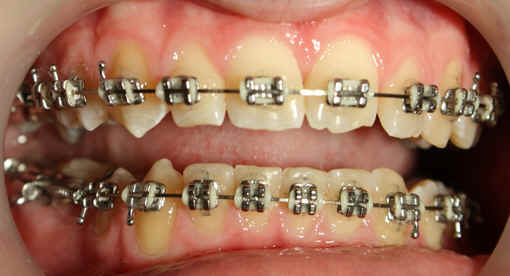

Intra-op 2009/09/10 U wire .018, L .020